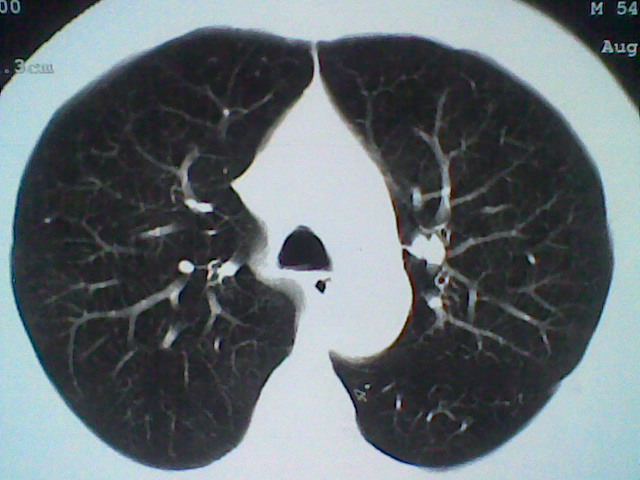

标题: CT21512:支扩伴感染?

患者女。咳嗽数天,咯血半天。

我们报的是支扩伴感染?

支持 支气管扩张并感染。

支持楼主意见,考虑支气管扩张并感染。

支气管扩张并感染。

可以诊断为支扩。